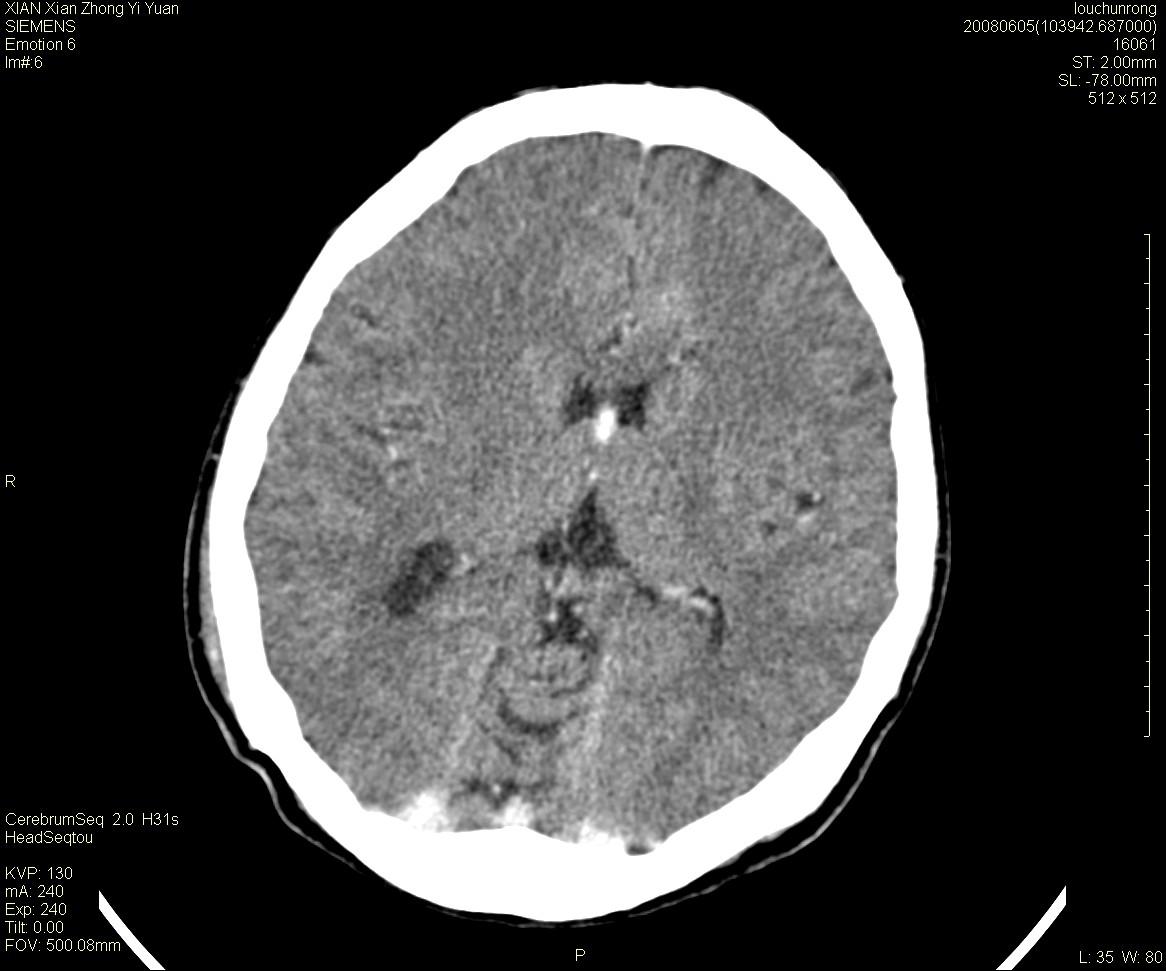

标题: CT13860:F52Y,,头外伤致头晕半天,以前无不适。 [打印本页]

标题: CT13860:F52Y,,头外伤致头晕半天,以前无不适。

层厚2mm。

左侧侧室内血管异常增粗,考虑血管变异或血管瘤可能,余未见异常

大家看左额叶大脑镰旁高密度影

两侧脑室体部距离增宽,胼胝体发育不良?

中线附近、枕叶近枕骨处及脑内多发点条状强化影,考虑血管异常?

大脑大静脉池内的密度不均,双侧脑室增宽,我看右异常这块。战友们看看

侧脑室前角变形、变窄,考虑侧脑室粘合;余未见明显异常。